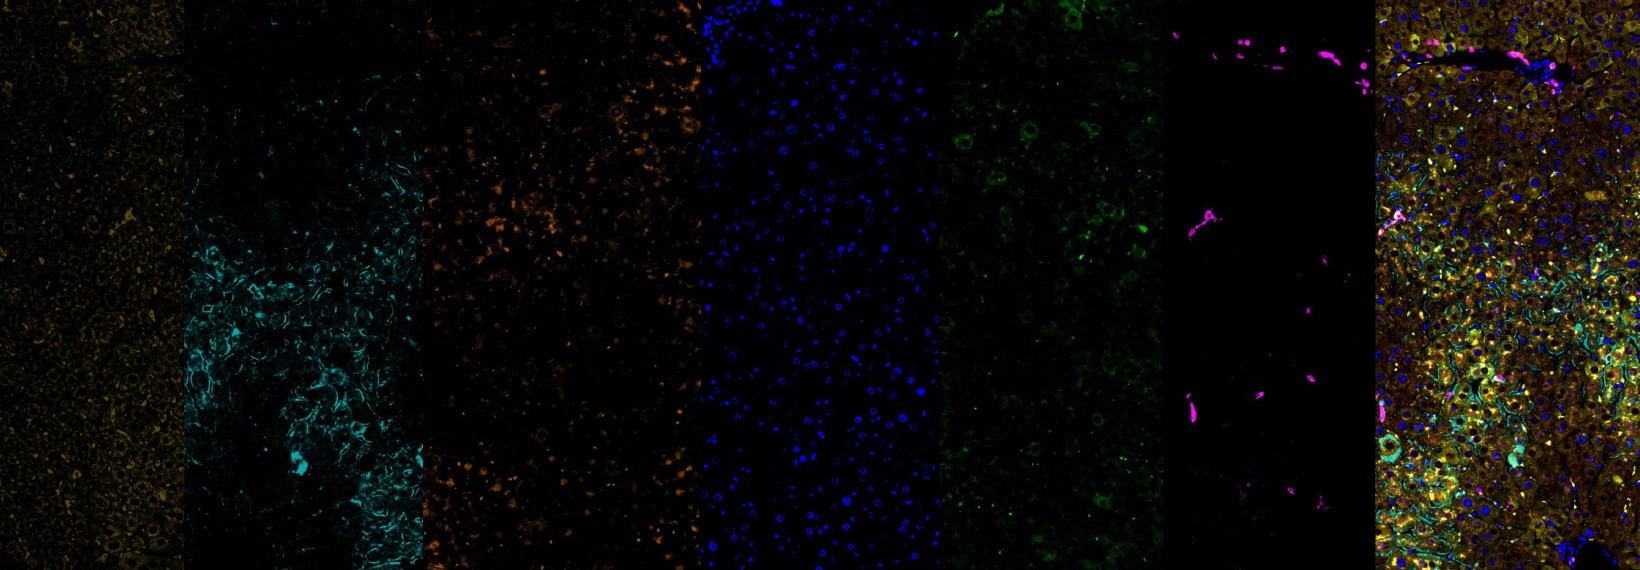

Immunofluorescence (IF)

Multiplex_CD8a (Green, AF488), HepBC (Red, AF594) HepBS (Magenta, AF647) CD11c (Yellow, AF750)